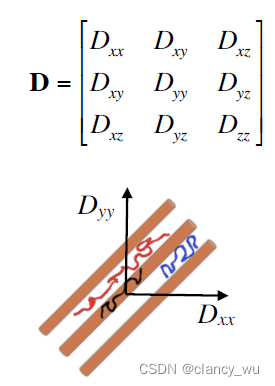

DTI的原理基础是弥散张量模型,Diffusion Tensor Model。即在每一个体素里计算它的

在计算的时候,是按照定义的坐标系进行计算,XYZ坐标系:

其实还需要计算它的解剖学坐标系:

这样,通过这些定义的坐标系,我们就能用公式来表达各向异性和各向同性:

由此,可以得出各向异性的表达公式。各向异性的全称其实是Fractional Anisotropy,FA值,在[0, 1]之间。MD是平均扩散率